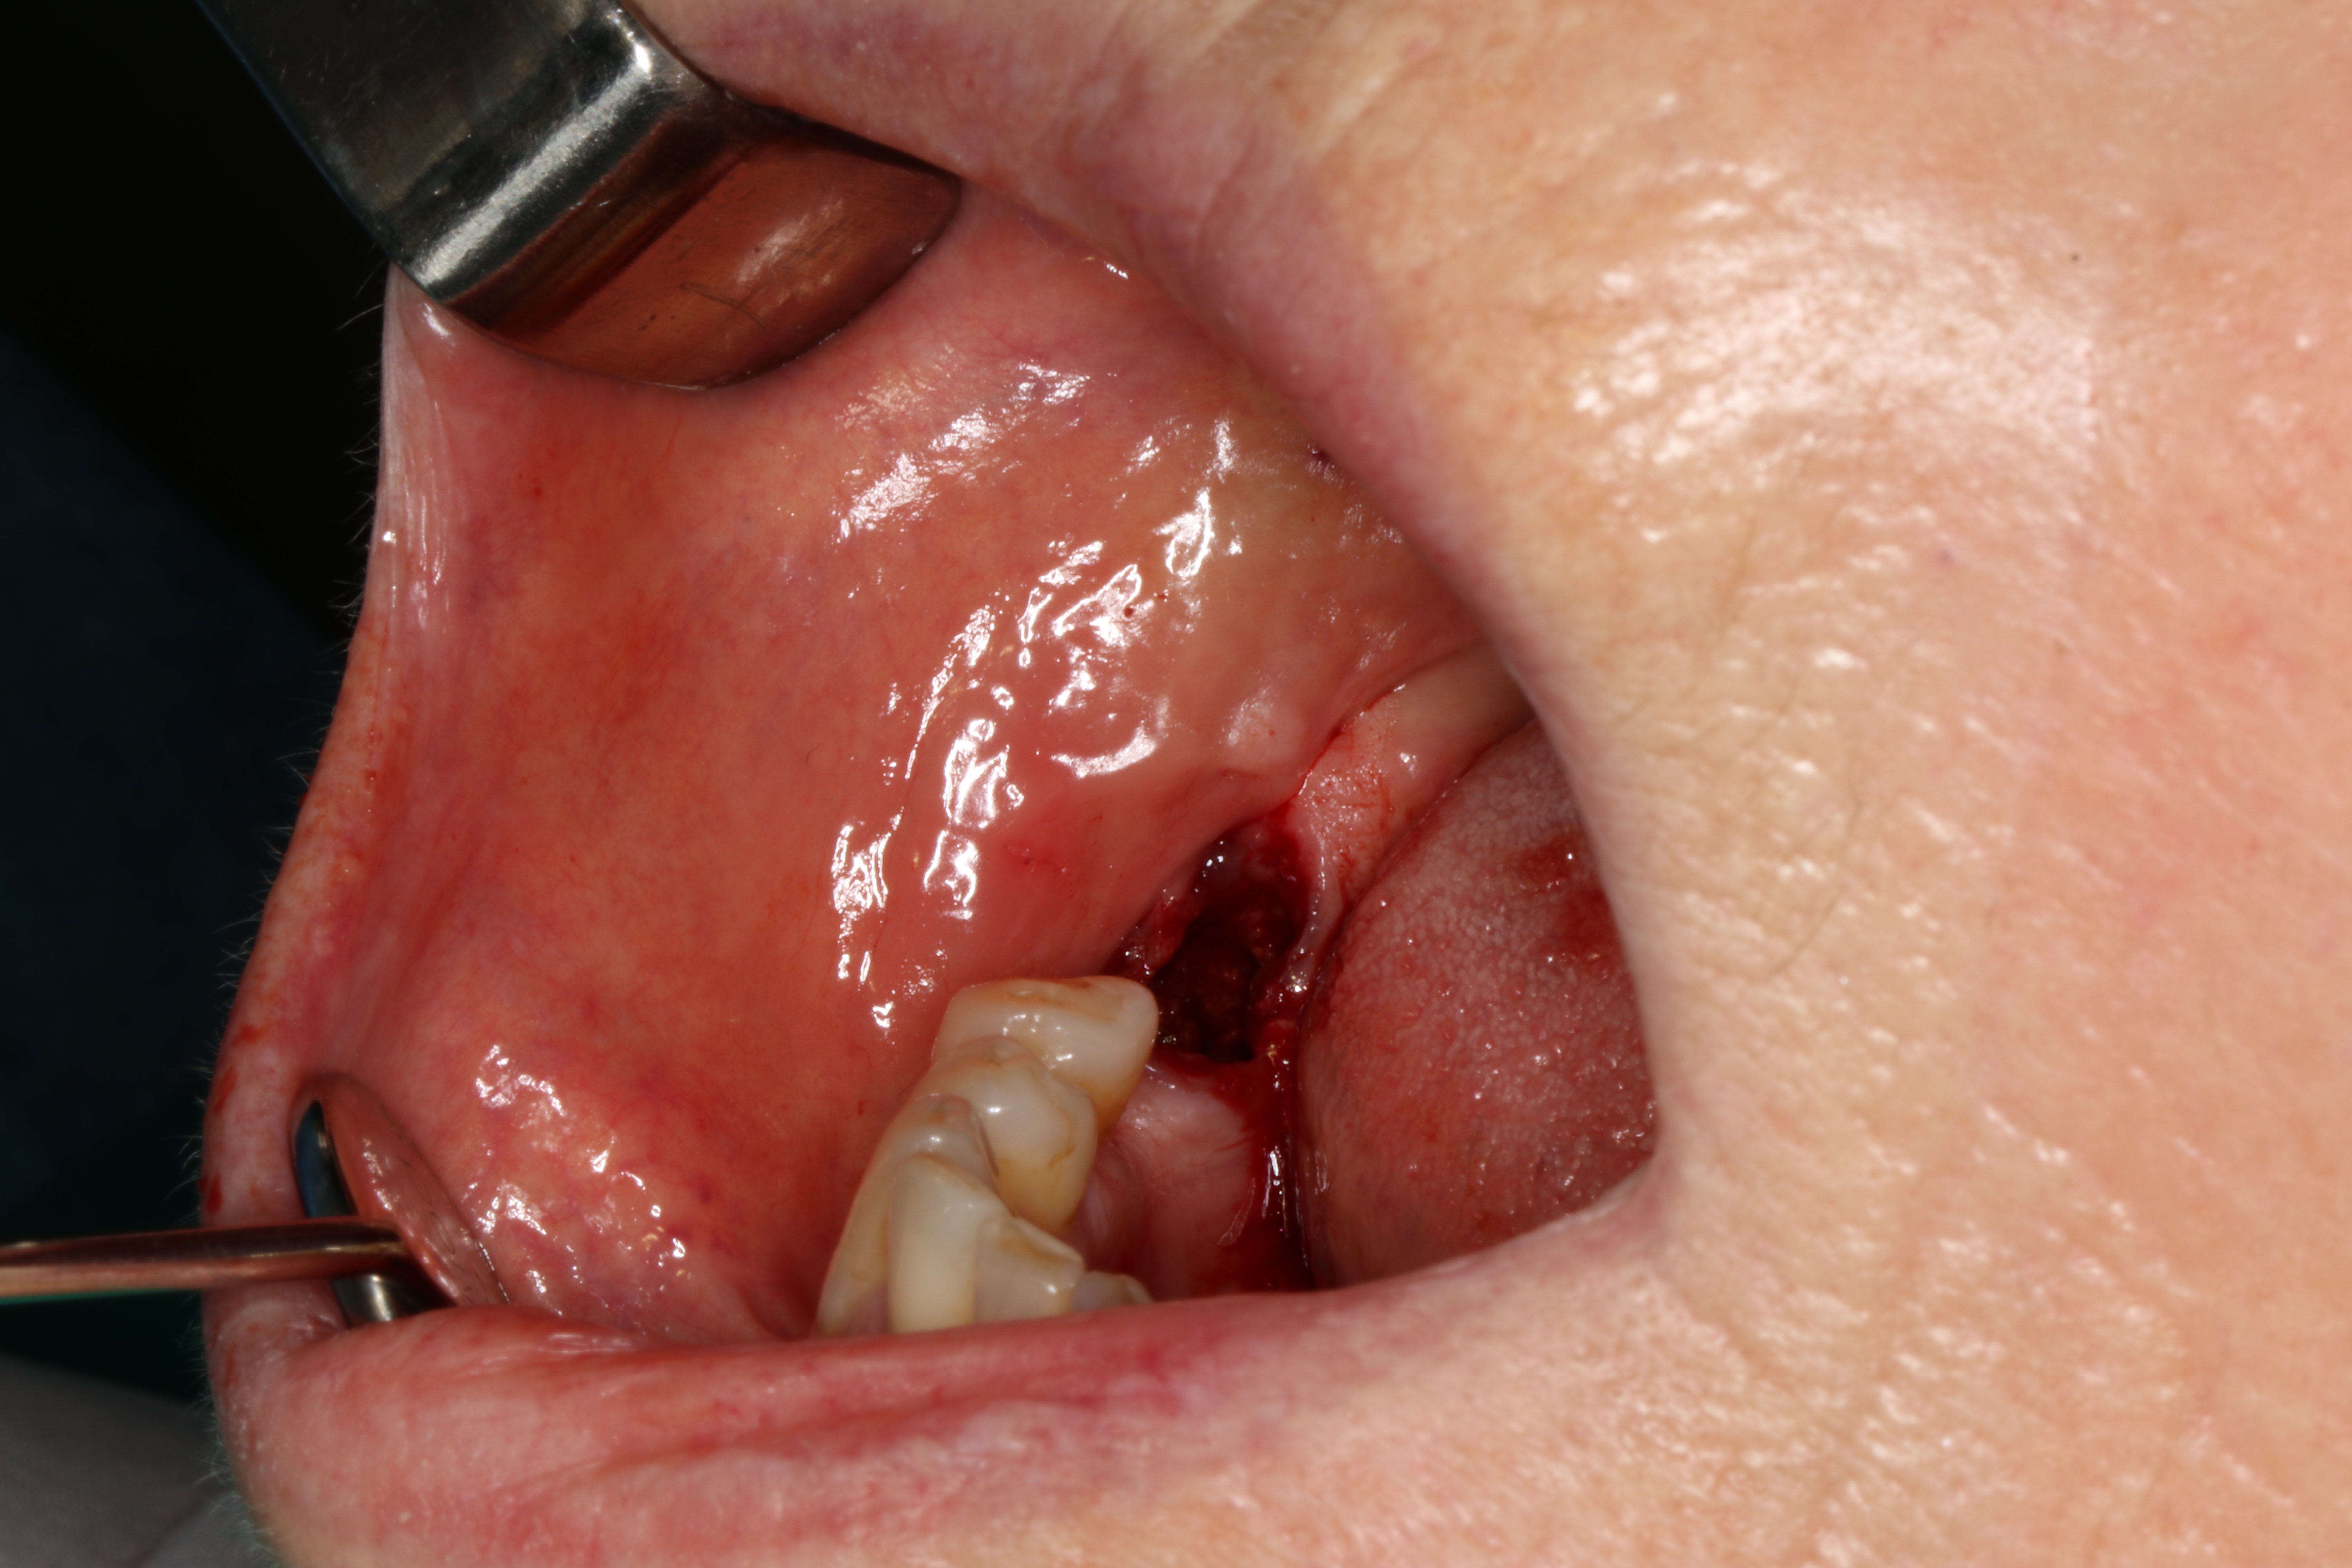

W znieczuleniu nasiękowym i przewodowym z zastosowaniem dentocaine 4% (podano 4 ampułki) usunięto minimalnie inwazyjnie ząb 47. Następnie wykonano płat śluzówkowo-okostnowy i dotarto do jamy torbieli. Usunięto ząb 48 oraz wyłuszczono zmianę, którą następnie oddano do badania histopatologicznego. Ranę zaopatrzono szwami 4-0 oraz opatrunkiem chirurgicznym (ryc. 2).

Ryc. 2. Zdjęcia śródzabiegowe: a) okolica operowana; b) stan po usunięciu zęba 47; c) wykonanie płata śluzówkowo-okostnowego, widoczny ząb 48; d) wyłuszczenie zmiany, obecna gruba torebka łącznotkankowa; e) loża pozabiegowa; f) usunięte zęby 47 i 48; g) stan pozabiegowy; h) aspirat ze zmiany (grudzień 2020).